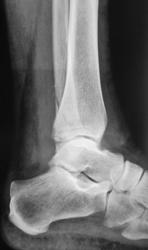

Пол пациента: Мужской пол Тип патологии: Травма Область исследования: Скелетно-мышечная система Методы исследования: Rg Травма. Пациент направлен на рентгенографию голеностопного сустава. https://radiomed.ru/sites/default/files/styles/case_slider_image/public/user/12/2.p4180015.jpg?itok=-HTogZ0n ID:21012 Пнд, 30/04/2012 - 13:14 #1 doktor-rentgen Не на сайте Был на сайте: 9 лет 2 месяцев назад Зарегистрирован: 06.07.2010 - 20:56 Публикации: 640 Перелом латеральной и задней(краевой перелом) лодыжки. А что за очаги просветления в метадиафизе б/б кости? Пнд, 30/04/2012 - 19:16 #2 Дмитрий К Не на сайте Был на сайте: 6 лет 5 месяцев назад Зарегистрирован: 27.10.2011 - 10:17 Публикации: 120 + перелом пяточной кости Пнд, 30/04/2012 - 21:18 #3 doktor-rentgen Не на сайте Был на сайте: 9 лет 2 месяцев назад Зарегистрирован: 06.07.2010 - 20:56 Публикации: 640 Дмитрий К wrote: + перелом пяточной кости Ткните где перелом, пожалуйста Втр, 01/05/2012 - 00:12 #4 Александр Викторович Не на сайте Был на сайте: 8 лет 2 недели назад Зарегистрирован: 31.07.2010 - 13:05 Публикации: 639 doktor-rentgen wrote: Дмитрий К wrote: + перелом пяточной кости Ткните где перелом, пожалуйста пятка цела Втр, 01/05/2012 - 13:52 #5 surgeon23 Не на сайте Был на сайте: 13 лет 6 месяцев назад Зарегистрирован: 25.04.2012 - 17:09 Публикации: 69 задний край и латеральная лодыжка. Пятка целая перемены - это единственное постоянство, которое нам дано Втр, 01/05/2012 - 20:54 #6 Катенёв Валенти... Не на сайте Был на сайте: 7 лет 4 недели назад Зарегистрирован: 22.03.2008 - 22:15 Публикации: 54876 surgeon23 wrote: задний край и латеральная лодыжка. Пятка целая Да, "кусочек" от задней лодышки не отвалился, но перелом есть.

Перелом латеральной и задней(краевой перелом) лодыжки. А что за очаги просветления в метадиафизе б/б кости?

задний край и латеральная лодыжка. Пятка целая

Да, "кусочек" от задней лодышки не отвалился, но перелом есть.